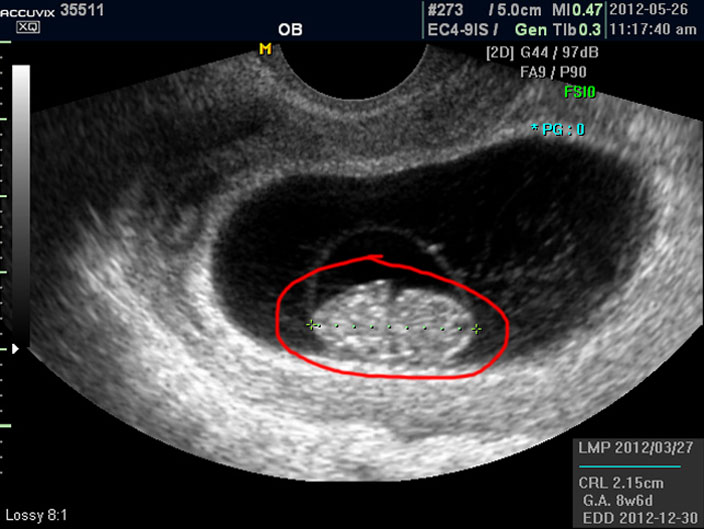

태아의 크기는 우측 하단에 실제 크기가 나와 있지만 아래 사진에서 빨갛게 표시한 부분의 안에 보이는 눈금이 1cm입니다.

이런 기준이나 지표들이 표시되는 것은 초음파 장비마다 조금씩 차이가 있고 위치도 다르지만 대개 비슷한 모양이라 한가지를 알면 다른 기종에서도 감상에 그리 어렵지는 않습니다.

참고로 저희는 국산 장비인 메디슨의 고급 기종인 아큐빅스라는 장비를 사용하고 있습니다.